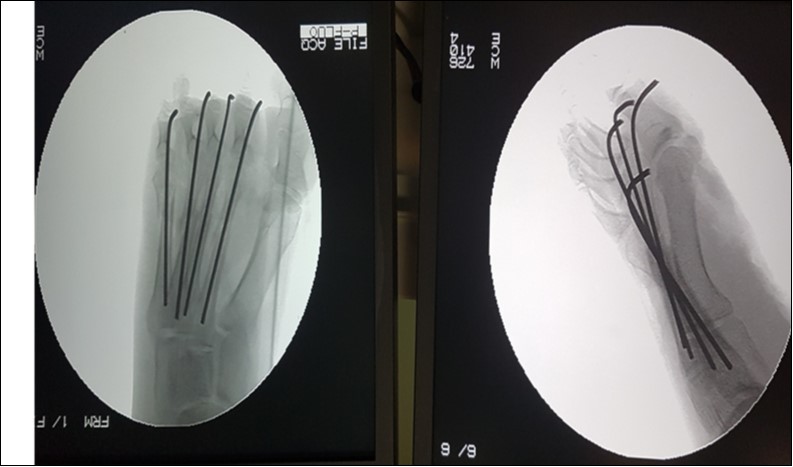

The open foot injuries in this study were treated by initial wound debridement followed by other procedures depending on the nature of the injury. Lacerations were debrided and sutured; where tendons were severed they were repaired as necessary, using standard repair methods. Open fractures were, after debridement, stabilized with K-Wires and thereafter, reinforced with a Plaster-of-Paris slab. Where skin defects could not be sutured, wound coverage was achieved by split skin grafting. None of the 81 patients studied required flap cover for a soft tissue defect. (Figure 1, Figure 2).

Figure 2.Check x-rays, anteroposterior and lateral views of the open right metatarsal fracture in figure 1, showing stabilization with 2.0-mm kirchner wires.